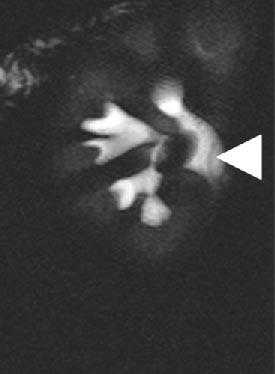

Гиперплазированные колонны Бертини могут выступать из паренхимы, и на УЗИ, на КТ нативных изображениях и нефрографическую фазу возникают подозрения на опухоль почки.

В кортикомедуллярную фазу данные подозрения могут быть опровергнуты. Ниже представлен случай верблюжего горба на УЗИ и КТ.

Представлен другой случай на КТ изображениях в нефрографической фазе есть основания утверждать, что это опухоль, но на кортикомедуллярной становится ясно, что это псевдоопухоль.